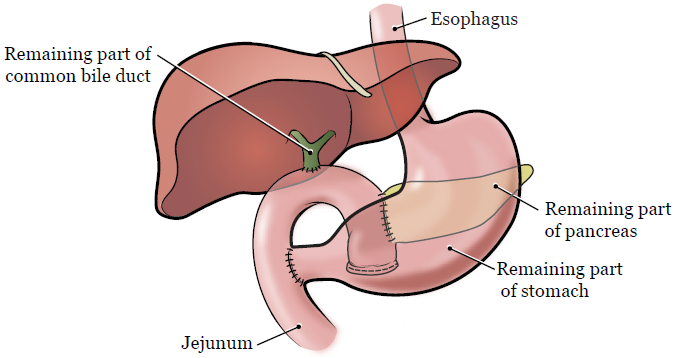

Фотографии медицинских исследований инсулиномы и синдрома Триады Уиппла